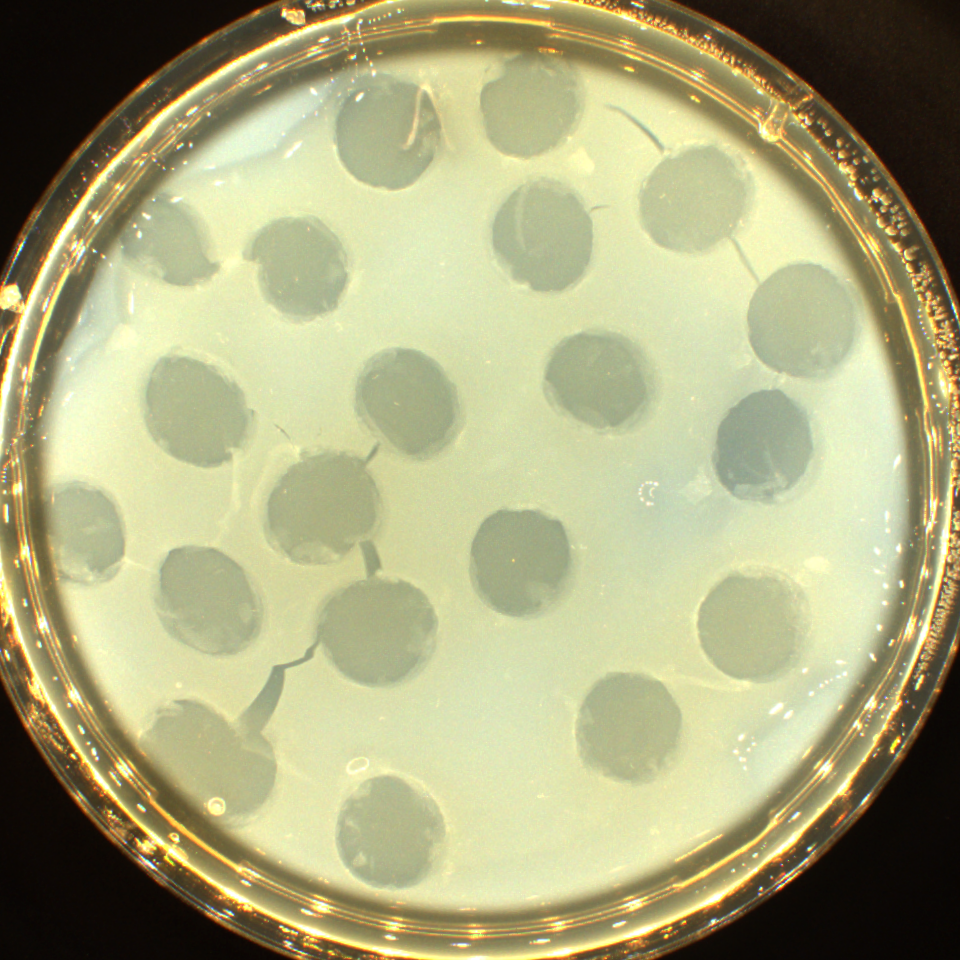

Bei diesem Prozess wird die Bakterienzelle vernichtet, was man im rechten Bild erkennen kann. Bakteriophagen sind sehr wirtspezifisch, das heißt Bakteriophagen, die z.B. Clostridium perfringens zum Vermehren benötigen, können keine andere Bakterienart zerstören. Auf dem fotografierten Agar ist ein Clostridium perfringens-Rasen gewachsen und auf acht Felder wurden Cl. perf.- Monophagen aufgetropft. Auf sechs Feldern ist zu erkennen, dass die aufgetropften Phagen die Clostridien lysiert haben. Zwei weitere Felder sind nach der Inkubationszeit immer noch mit einem geschlossenen Bakterienrasen verblieben, wonach zu urteilen ist, dass diese Monophagen nicht für den Erregerstamm geeignet sind und auch nicht für den Phagencocktail vorgesehen werden.

reine Bakteriophagenplaques